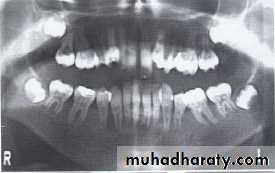

Paramolar blocking the eruption of 3rd molar.

MesiodensDistomolars(4th molar)

Mesiodens

Distodens or distomolarParamolar

Supplemental